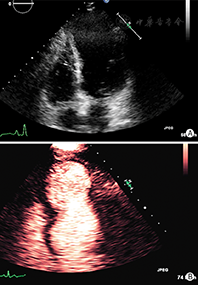

清晰地显示左心室心内膜边界是准确评价左心室功能的关键。国外临床试验表明,常规超声心动图检查时70%~90%的心血管超声图像不佳(图像质量不佳定义:在任何一个心尖长轴标准切面有2个或2个以上的连续心肌节段的心内膜结构不能清晰显示),通过使用造影剂后可明显提高诊断图像的解剖结构分辨率[15,16,17](图2)。在心脏解剖结构和功能异常状态判断存在疑问时也可考虑使用超声造影剂。当静息状态不能满意获得常规超声心动图图像时,造影剂用于左心室心腔造影尤其有帮助,这常见于肥胖、有肺部疾患、病情危重或接受呼吸机护理的患者。如果在这些患者中优化了换能器频率、扇扫宽度、图像深度和聚焦位置,心脏超声图像质量仍不理想,应当考虑使用造影剂。负荷超声心动图检查达峰值负荷时图像质量不理想的情况常较明显,此时使用造影剂将明显提高图像质量、增强判断信心和诊断准确性。此外使用造影剂将明显提高有经验和无经验医师解释图像的重复性和准确性[18,19,20]。